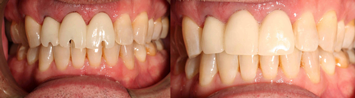

Figure 14 through Figure 18 show a partially dentate patient for whom a fully digital workflow was utilized. This 47-year-old male presented with root blunting and mobility of teeth Nos. 7, 8, and 9 (Figure 14). A thermoplastic clip was attached during the CBCT, and an intraoral scan was taken and superimposed on the CBCT. The case was then planned in the navigation planning software (Figure 15). Once the teeth were extracted, intraoral scanning was performed. The intraoral scan was imported into lab software (Figure 16), and a PMMA milled screw-retained prosthesis was fabricated. The prosthesis was placed the next morning (Figure 17). Two months later, a new intraoral scan was taken to capture the mature soft tissue, and the final milled titanium abutment and restoration were delivered (Figure 18).

Fig 14. Preoperative view of a partially dentate case. Patient with root blunting and grade 3 mobility.

Figure 14

Fig 17. Views of the milled PMMA screw-retained provisional restoration. Note the screw access holes in the incisor edges (left panel). (Images courtesy of Dr. Kim Knoll.)

Figure 17

Fig 18. Placement of the final prosthesis. Milled titanium abutments (left panel) and Emax crowns (right panel). (Images courtesy of Dr. Kim Knoll.)

Figure 18